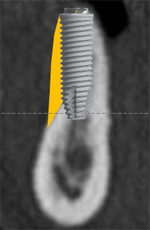

インプラント埋入前にサイナス部分にGBRを行い、骨が出来上がるのを待ってからインプラント治療を実施。

- 治療前の骨が足りていない状態

- サイナス部分にGBRを施し骨ができた状態

- 骨生成完了後インプラントを埋入し治療終了

- 主訴

- 上顎臼歯部の67欠損となり、上顎洞までの距離が不足したためインプラントの早期埋入が不可能であった

- 治療内容

- 上顎頬側よりラテラルウインドウ法で上顎洞底挙上術を行い2本のインプラントの埋入を行なった

- 治療費用

- 上顎洞底挙上術:150,000円(税別)、インプラント埋入1本:200,000円(税別)

- 治療期間

- 埋入手術までに6ヶ月